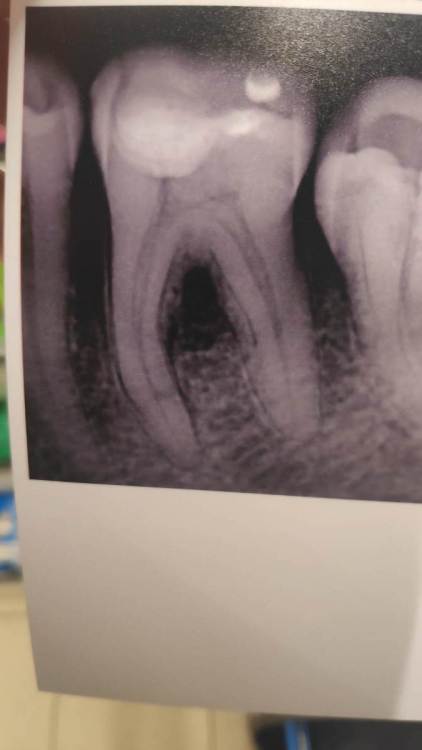

Расшифровка снимка (Глубокий кариес)

Здрасивуйте, сначала подозревали пульпит, но потом решили, что глубокий кариес. Сделали временную пломбу на 1.5 недели, боль прекратилась, осталась только при сильном надавливании. Чувствительность осталась. Врача сказала "Ок" и поставила постоянную пломбу. А через сутки зуб снова заболел, точнее начал ныть с утра еще до еды. Пошел в другую клинику неподолеку и там сделал снимок.

На консультации в частной клинике сказали что-то про близость канала к пдомбе и что что-то воспалилось, надо долечить.  Поскажите, это была ошибка стоматолога, которая ставила пломбу?